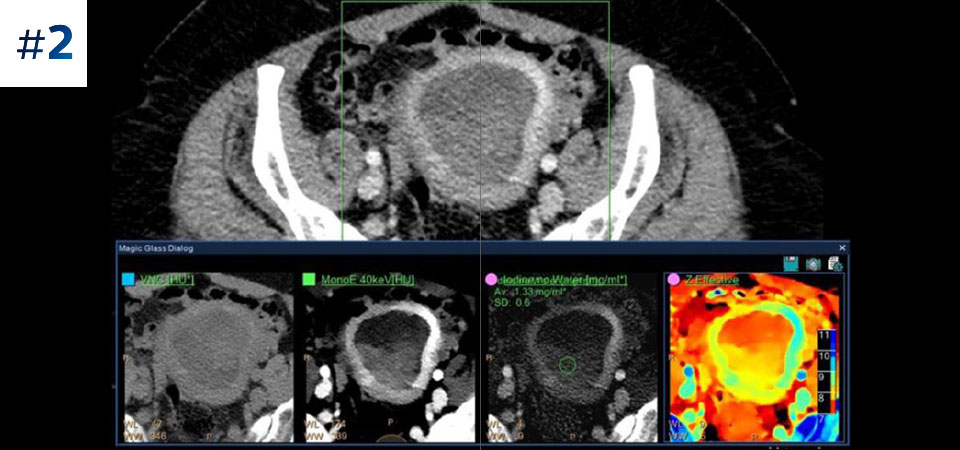

Neck mass